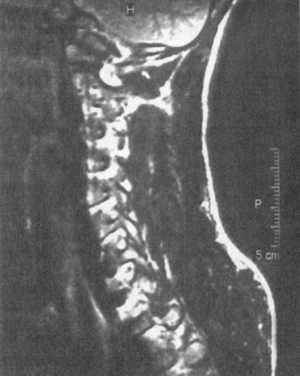

Ценную информацию о состоянии вывихнутых позвонков и спинного мозга дает

МРТ (рис. 2.6, 2.7). МРТ позволяет определить наличие зон ишемии в спинном

мозге (рис. 2.8, 2.9), состояние ликвородинамики (рис. 2.10).

Рис. 2.6. Переломо-вывих скользящий

C5-C6, позвонков со смещением тела С5 кзади с грубой компрессией спинного

мозга на данном уровне |